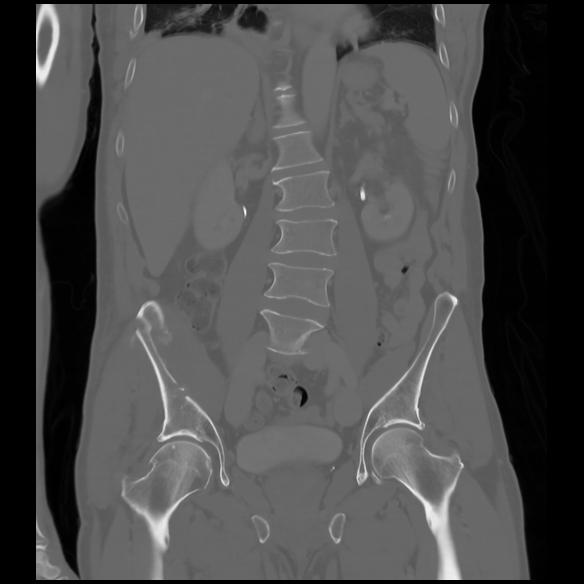

6 CUERPO,CE,Coronal,3.000,CUERPO,Coronal,